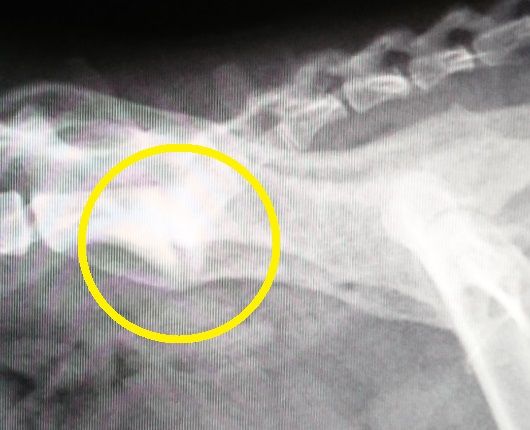

2015年:10歳のレントゲン

背骨と尻尾の付け根の骨の状態の経過を年を追って見てみると、若い頃は、骨と骨の隙間もしっかり開いてましたが、2015年のレントゲンでは、先ずは、隙間がかなり狭くなって来ており、更に、2016年のレントゲンでは、骨の下の部分に突起が、これを我が家ではトケトケと呼んでいます。